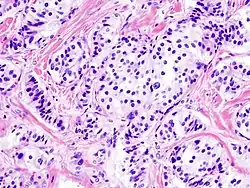

![]() Панкреатический островок, окраска гематоксилин-эозином. | |

Гистологическая картина

- Патогистология

Панкреатическая инсулинома Окраска инсулиномы Chromogranin A - Histopathology of pancreatic endocrine tumor (insulinoma). Insulin immunostain.